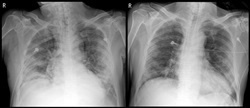

완치자 2명 중 김모 씨(71·남자)는 말라리아치료제와 에이즈치료제 등 항바이러스 치료를 받았으나 상태가 좋아지지 않아 세브란스병원으로 이송됐다. 도착 당시 호흡 속도는 분당 30회 이상(정상 성인의 경우 20회 이하)이었는데, 흉부 X-ray검사에서 양쪽 폐 모두에서 심각한 폐렴 증상을 보였다.

이에 최 교수팀은 코로나19 완치 판정을 받고 2주가 지난 남성의 회복기 혈장 500ml를 김 씨에게 12시간 간격으로 두 번에 걸쳐 투여했다. 스테로이드 치료도 병행했다. 이후 김 씨는 열이 떨어지고, CRP도 5.7mg/L로 떨어졌다. 흉부 X-ray 검사상 양쪽 폐도 더 이상 나빠지지 않았고, 혈장 투여로 인한 부작용도 없었다.